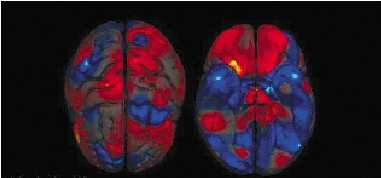

男女大脑有大小

打开意念之门